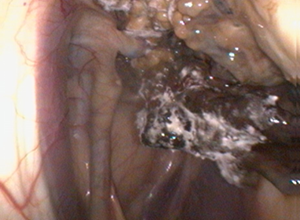

Die sog. Nasenmuscheln sind ein Bestandteil der Nasennebenhöhlen des Pferdes. Sie grenzen an die Nasengänge und haben eine besonders filigrane Wand. Bei chronischen Entzündungen der oberen Atemwege oder durch Verletzungen kann es dazu kommen, dass Anteile der Nasenmuscheln nicht mehr durchblutet werden und absterben. Es entstehen sog. Sequester, d. h. totes Gewebe, dass der Körper des Pferdes abstoßen möchte, dies aber häufig nicht vollständig schafft. Die Tiere fallen durch vermehrten Nasenausfluss auf der betroffenen Seite und üblen Geruch beim Ausatmen auf. Mittels Endoskopie kann man die betroffenen Areale häufig einsehen und das abgestorbene Gewebe lösen. Über den Arbeitskanal des Endoskops werden feine Instrumente vorgeführt, um den Sequester zu greifen und so zu entfernen. Ist dies vollständig geschehen, heilen die Bereiche innerhalb kürzester Zeit ab, ohne das negative Folgen für das Pferd entstehen.

Der Begriff beschreibt eine Ansammlung von Eiter im Luftsack. Fast immer ist der Grund hierfür eine Druseerkrankung. Denn unter dem Boden des Luftsackes liegen die sogenannten Retropharyngeallymphknoten, welche zusammen mit den Kehlgangslymphknoten die am häufigsten bei der Druse betroffenen Lymphknoten sind. Der Erreger führt zur Abszessbildung im Lymphknoten. Platzt der Abszess anschließend auf, entleert sich der Eiter in den Luftsack hinein. Meistens entleert dieser sich anschließend über die Luftsackklappe in den Rachenraum und fließt von dort über die Nüstern ab, wo er dann als eitriger Nasenausfluss ein- oder beidseits sichtbar wird. Ca. 3 Wochen nach den letzten Symptomen ist die „Selbstreinigung“ des Körpers abgeschlossen und der Luftsack wieder sauber. In Einzelfällen funktioniert dies jedoch nicht, so dass der Eiter im Luftsack verbleibt, eintrocknet und sogenannte „Chondroide“ („Eitersteine“) bildet. Um das festzustellen, kommt auch die Endoskopie zum Einsatz, denn abschließend ist immer eine endoskopische Kontrolle der Luftsäcke mit Entnahme von Spülproben zu empfehlen. Mehr Informationen zur Druse finden Sie hier: Link